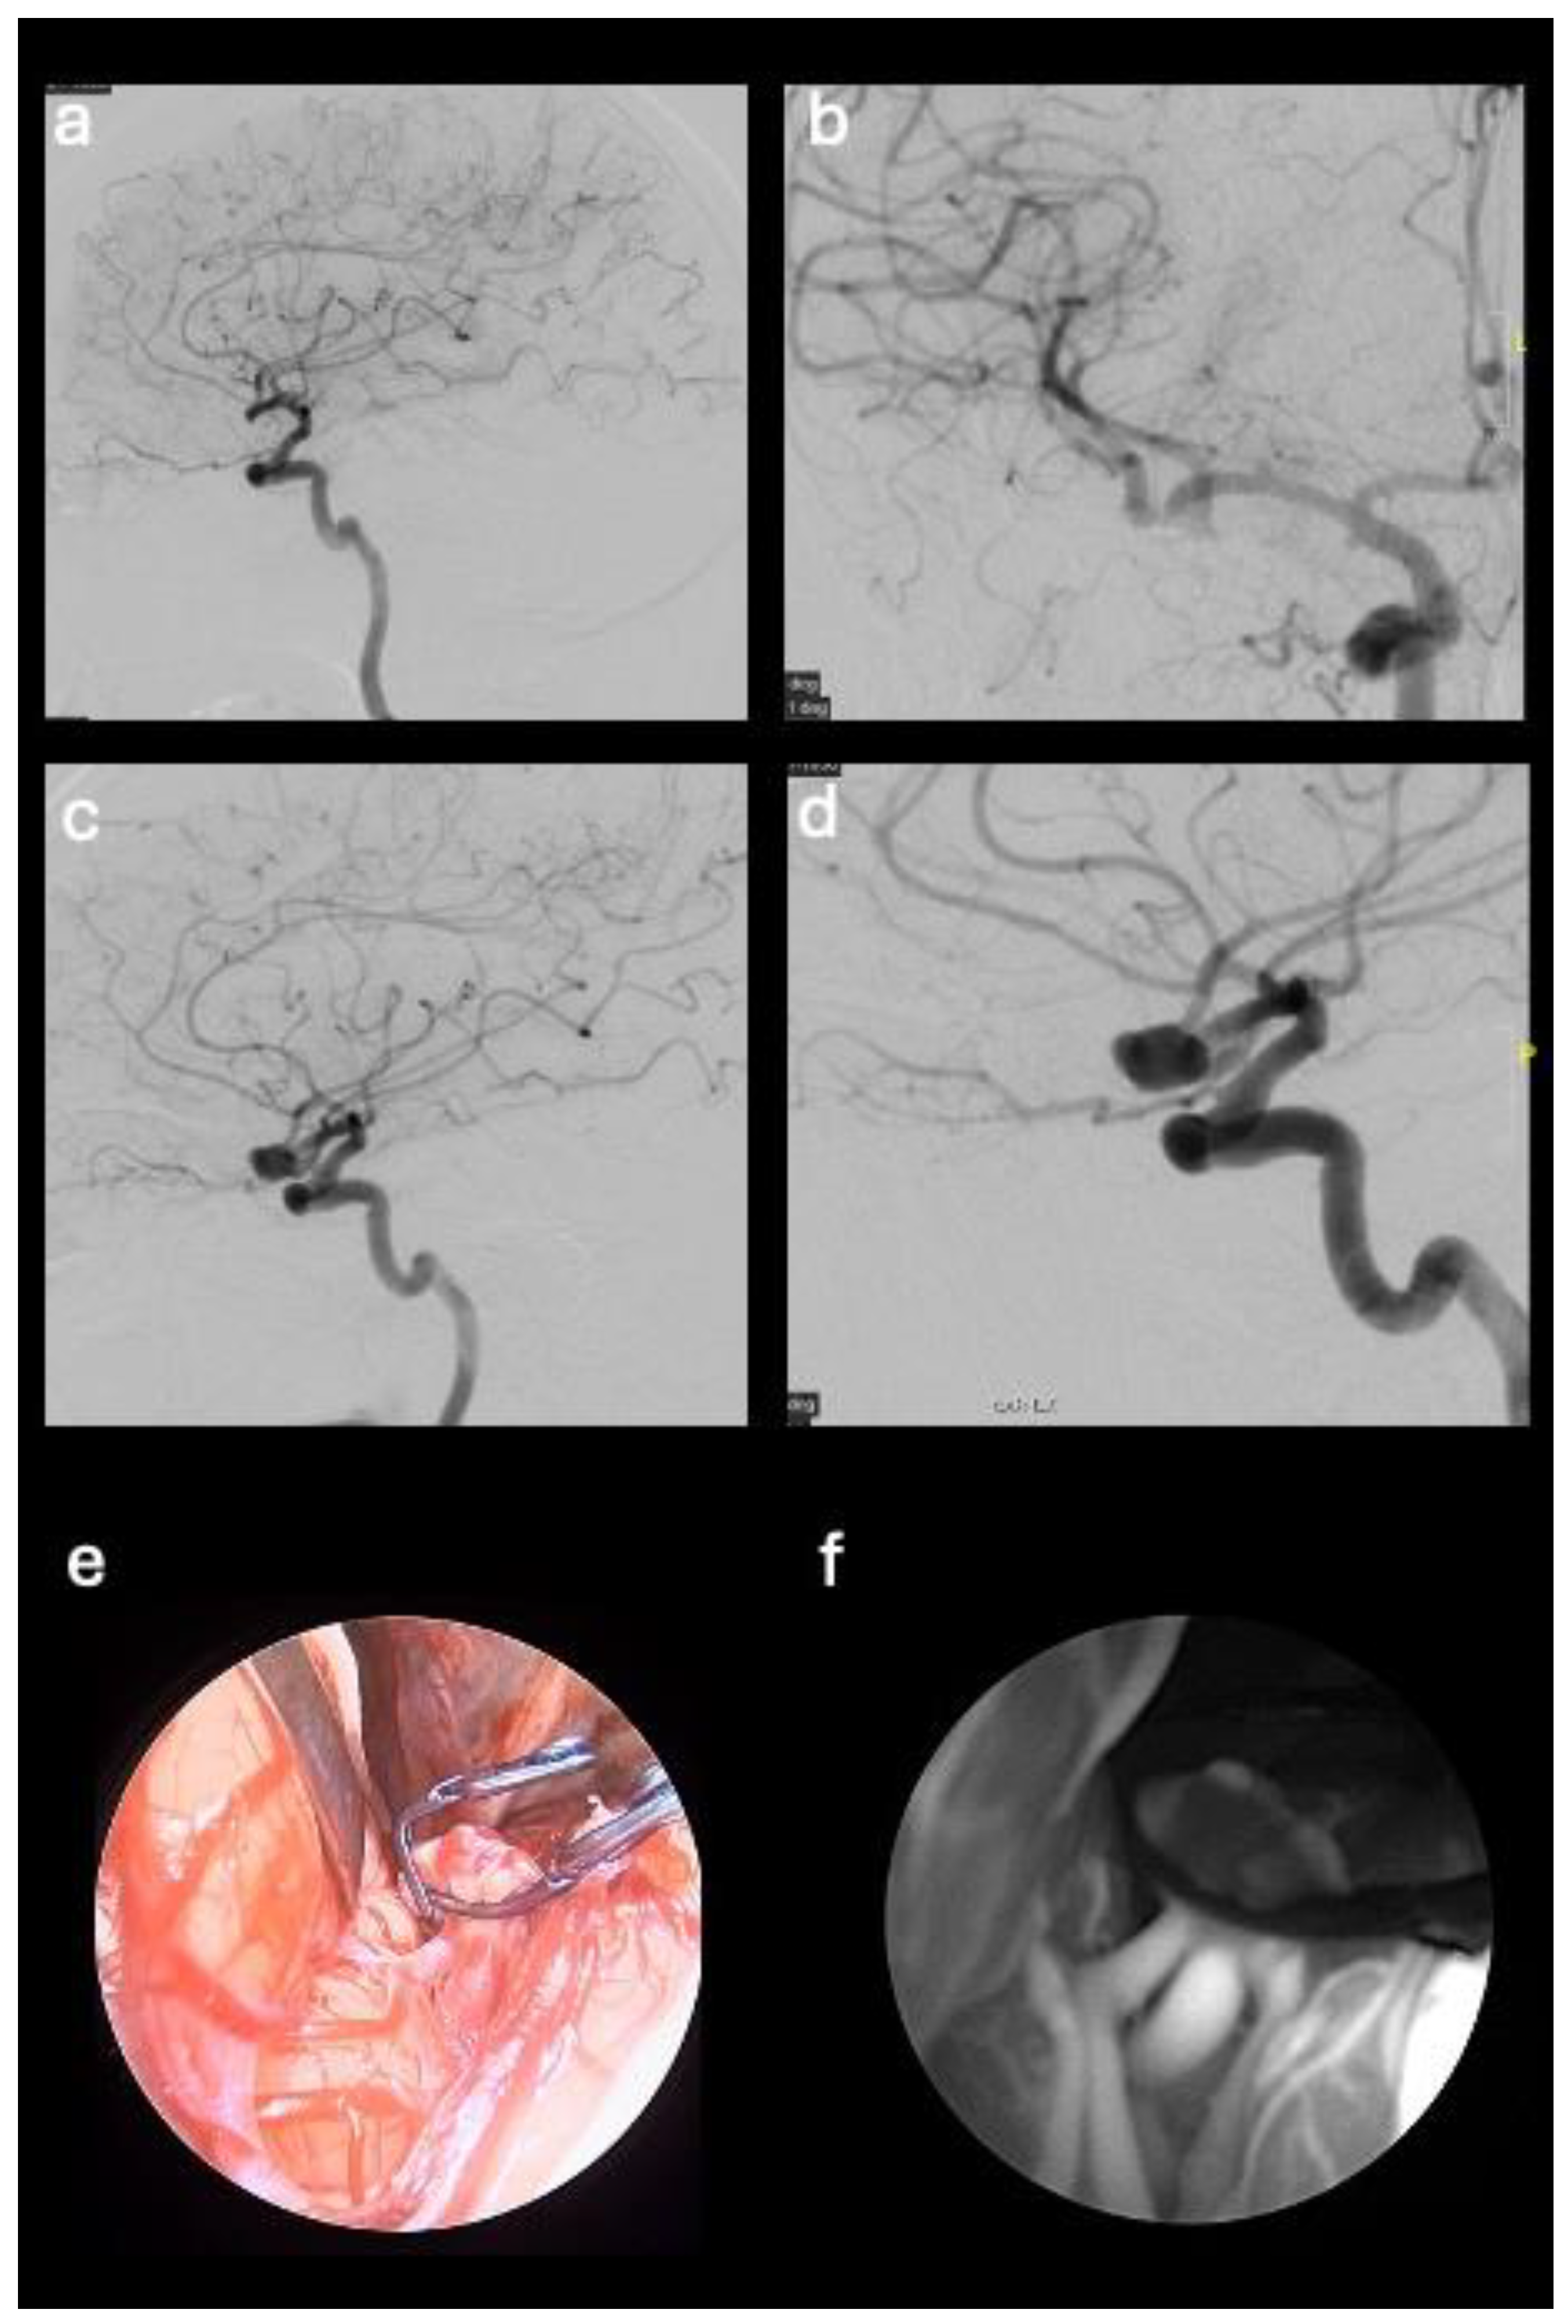

Figure 3. Pre- and post-operative DSA images that show right multilobed middle cerebral artery aneurysm (M1-M2 union) (a-b); Post-operative DSA image of the excluded aneurysm (c-d). Standard endoscopic view (e) and endoscope in SPY mode (f).